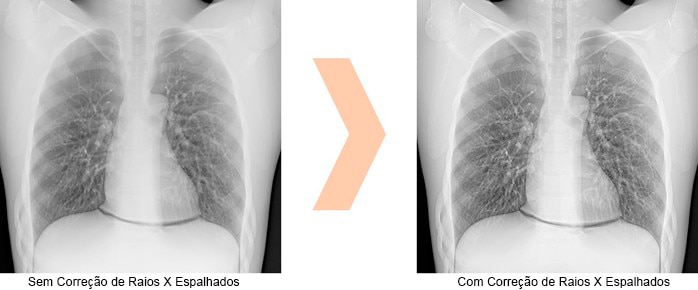

Correção da dispersão dos Raios-X – Radiografia Sem Grade (Opcional)

O sistema pode ser equipado com uma função que remove o ruído da radiação espalhada e melhora o contraste da imagem, permitindo realizar exames sem o uso de grade. Essa funcionalidade facilita o manuseio dos FPDs, tornando o processo mais ágil e prático.